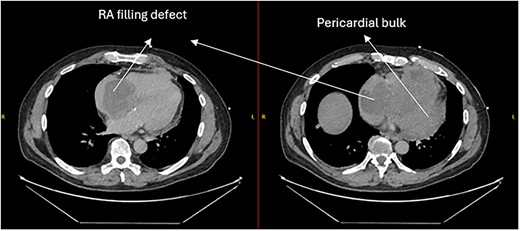

Follow-up CT scans were undertaken during chemotherapy that showed continued reduction in the size of the RA tumour, as demonstrated in Figs 4 and 5. The pericardial mass following chemotherapy is visualized in Fig. 6.

Post-operative CT scan during chemotherapy showing reduction of size RA bulk.